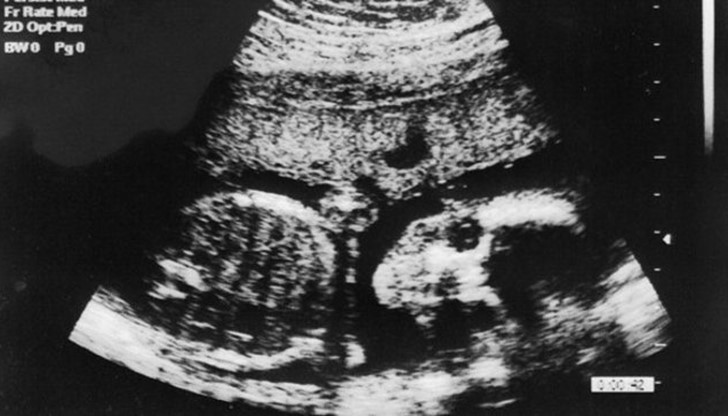

Насочен ултразвук с висока интензивност би могъл да служи и за освобождаване на медикаменти от специални капсули вътре в злокачествените образувания. При терапията се използват звукови вълни с честоти над границата, доловима за човешкото ухо. При ниска мощност ултразвукът генерира изображения на вътрешни органи или на ембрион, който се развива в утробата на майката. При високи нива на енергия ултразвукът разрушава тъканта. Лъчите, които най-често са 10 хил. пъти по-мощни от прилаганите за наблюдение на бременност, нагряват и убиват клетките. Най-важното е, че това може да се направи на места дълбоко в органа, без да се засегне тъканта на повърхността, изтъкват изследователите.